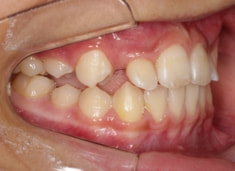

治療前

治療開始時